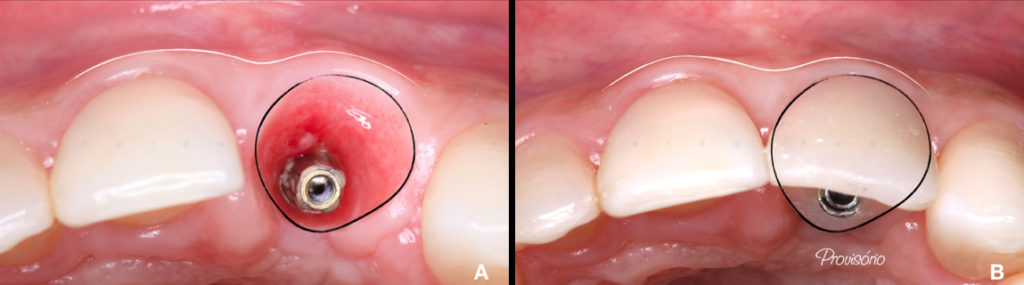

Em 15 dias após o manejo, removemos a sutura e aguardamos 25 dias para o início da fase de provisionalização que é a etapa de condicionamento do perfil gengival, que promove a estabilidade e os contornos dos tecidos para uma futura coroa definitiva (Furze, 2019).

Utilizamos inicialmente um pilar de titânio anti-rotacional (AR) provisório para a captura do dente que estava na contenção estética removível. Assim, delimitamos todos os contornos e subcontornos das áreas críticas e subcríticas favorecendo a migração coronal da gengiva, resultando em uma melhor condição estética na posição da margem cervical do tecido mole (Frizzera, 2018). Fig.6A/B/C